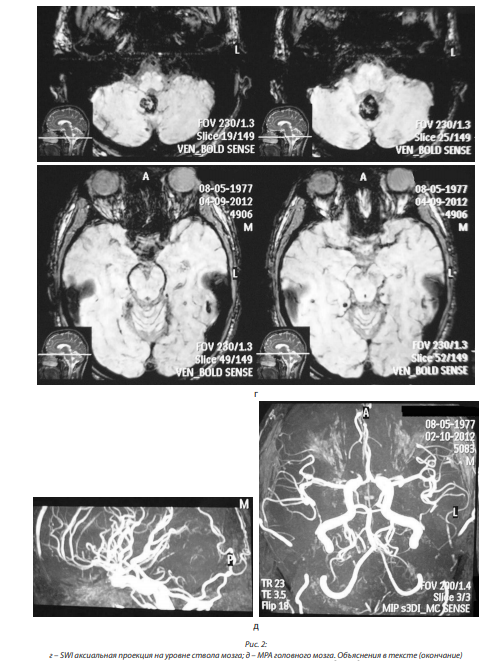

В сентябре 2012 г. выполнена МРТ головного мозга, заключение: большая кавернома в нижней половине червя мозжечка (размерами 21×18×18 мм). По сравнению с МРТ от апреля 2012 г. без видимой динамики. Множественные (не менее 10, размерами от 3 до 10 мм) каверномы в полушариях большого мозга. Венозная ангиома моста.

При МРА от октября 2012 г.: сужений, аневризм, патологической извитости магистральных артерий не выявлено; вариант отхождения левой задней мозговой артерии (ЗМА), сосудистая связь с каверномой отсутствует (рис. 2, а, б, в, г, д).

В сентябре 2013 г. МРТ головного мозга выявила симметричную, бивентрикулярную водянку; рубцово-глиозные изменения в области миндаликов мозжечка справа; отсутствие патологического накопления контрастного вещества, отсутствие расширения оболочечных пространств полушарий мозга; без динамики по сравнению с МРТ от декабря 2012 г. Не описаны имевшиеся признаки ГДО. МРА дополнительной сосудистой сети не выявила (рис. 4, а, б, в).

При МРТ головного мозга в сентябре 2016 г. выявлена умеренно выраженная компенсированная бивентрикулярная водянка; в проекции медиальных отделов правой гемисферы и червя мозжечка – зона постоперационных изменений размером 27×15×16 мм, со следами гемосидерина, правый выворот IV желудочка подтянут к зоне изменений, при контрастном усилении участков патологического накопления контрастного вещества не выявлено; атрофические изменения субкортикальных отделов обеих гемисфер мозжечка. Заключение: состояние после РТ ЗЧЯ справа, удаление каверномы червя мозжечка. Данных за рецидив не выявлено. Атрофические изменения субкортикальных отделов обеих гемисфер мозжечка (рис. 5, а, б, в).